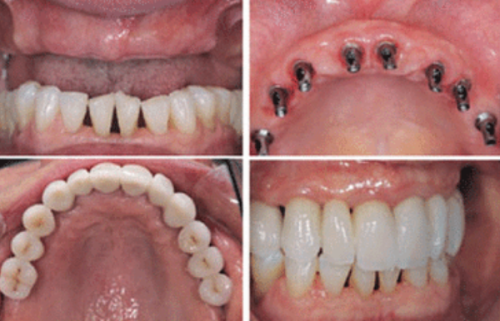

医生的技术水平和种植牙的品牌、质量也是重要因素。经验多的医生在种植过程中能够更精细地操作,提高种植牙的成功几率和使用寿命。而优质的种植牙材料通常具有更好的生物相容性和稳定性,也能为种植牙的长期使用提供保护。